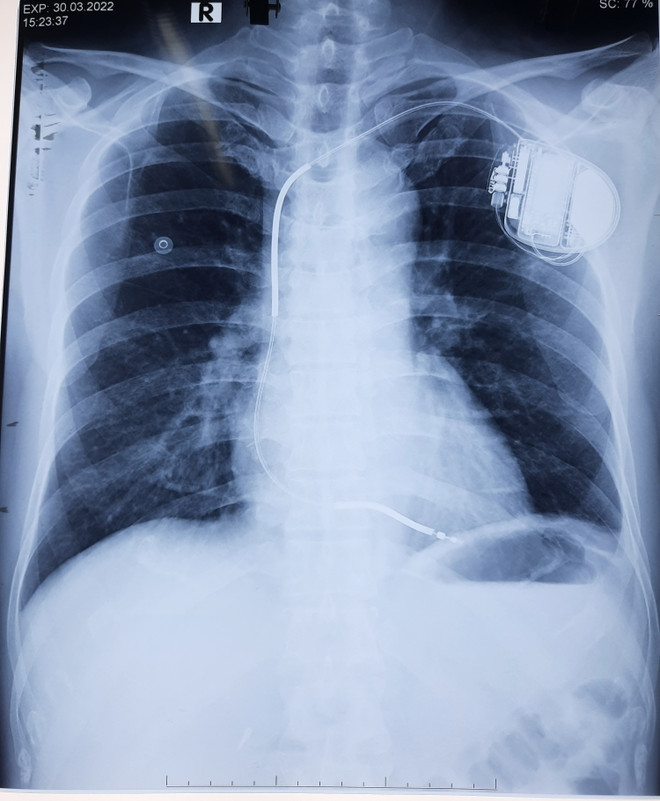

Cấy máy phá rung tự động, cứu sống bệnh nhân bị ngưng tim, ngưng thở ảnh 2Ảnh chụp X-quang bệnh nhân được cấy máy phá rung tự động (ICD). (Ảnh: TTXVN phát)

Máy ICD được cấy ghép dưới xương đòn, một dây điện cực kết nối từ máy vào buồng tim phải qua đường tĩnh mạch dưới đòn. Máy ICD ghi nhận và theo dõi tất cả mọi hoạt động điện học của tim.

Khi tim xuất hiện tình trạng rối loạn nhịp nguy hiểm, tín hiệu bất thường này sẽ chuyển tới máy ICD, máy sẽ phát dòng điện để cắt những cơn rối loạn nhịp, đưa trái tim trở về nhịp co bóp bình thường, ngăn ngừa đột tử.